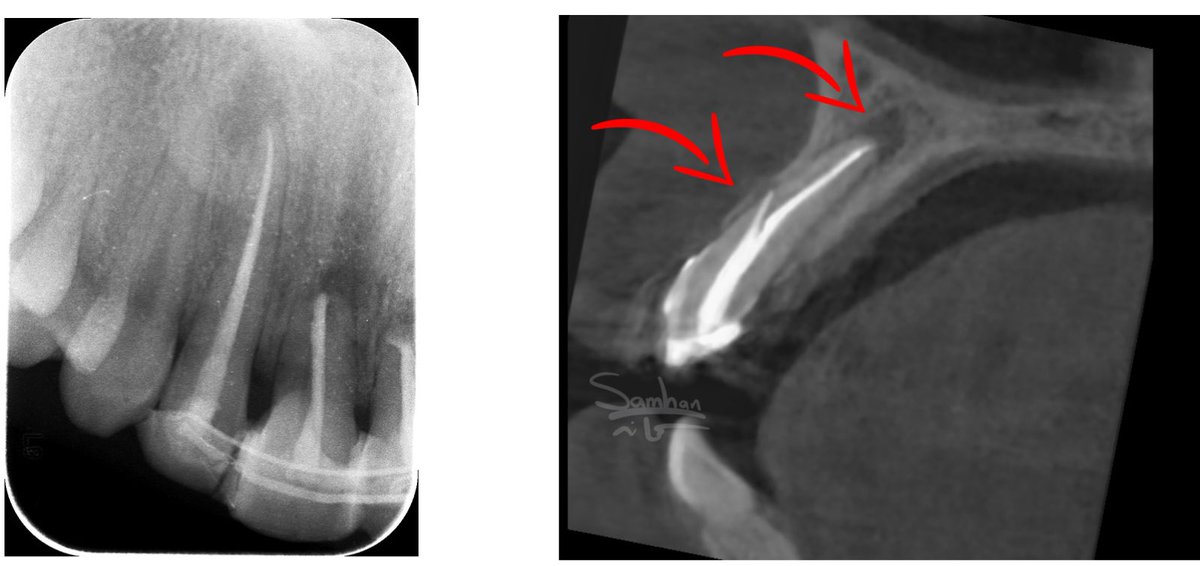

أحد أكبر التحديات اللي كنا نواجهها في تشخيص فشل علاج العصب،

إننا كنا نعتمد بشكل رئيسي على الأشعة العادية.

المشكلة إن الأشعة العادية ضعيفة جدًا في تحديد

بالضبط وين تآكل العظم اللي سببه تسرب البكتيريا.

أحيانًا يكون تآكل العظم واضح في نهاية الجذر…

لكن في حالات كثيرة، التآكل يكون في أماكن أخرى تمامًا:

• مرات يكون على جانب الجذر – بسبب قناة جانبية أو ثقب.

• مرات يكون بين الجذور Furcation

• ومرات… إذا كنا محظوظين وصار في Sinus tract،

نستخدم الـ GP لمعرفة اتجاه الخراج.

لكن حتى الـ GP ما يعطي الصورة كاملة،

لأن ممكن يكون في خراج ثاني بمكان مختلف واحنا ما ندري عنه.

وهنا كانت النقلة النوعية:

لما بدأنا نستخدم الأشعة المقطعية – CBCT،

أصبح التشخيص دقيق بشكل كبير.

معرفة مكان تآكل العظم مو بس تسهّل العلاج…

أحيانًا تغيّر خطة العلاج بالكامل.

لهذا السبب، في حالات فشل علاج العصب،

الـ CBCT مو مجرد خيار يساعد…

صار ضرورة في أغلب الحالات عشان نعالج السن بالطريقة الصحيحة.

هذه بعض الحالات اللي تبين اماكن الخراج.